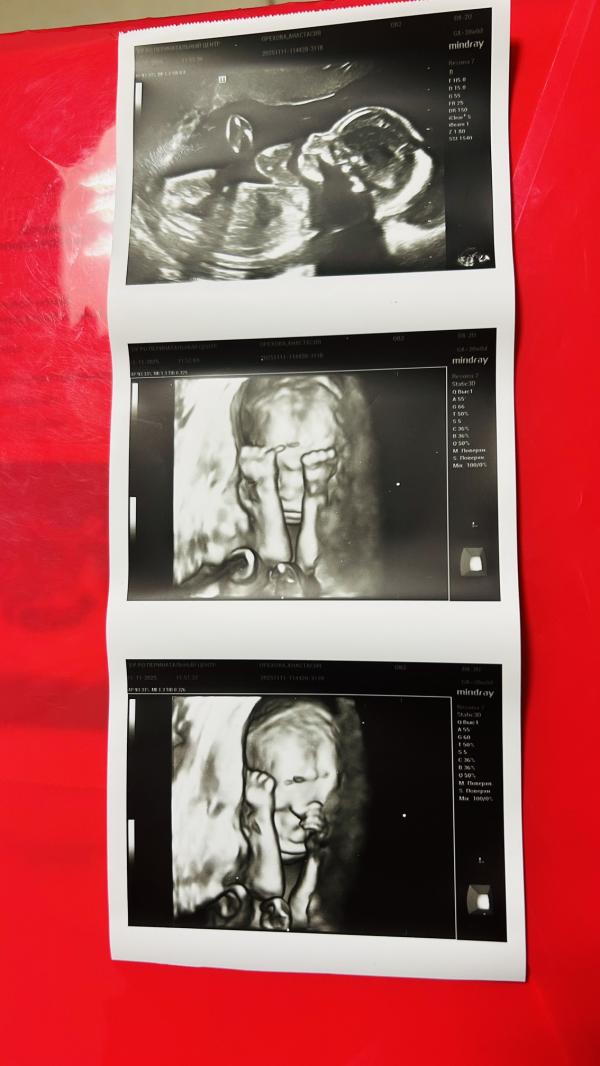

Второй скрининг при беременности: результаты и эмоции

Второй скрининг пройден

Все хорошо, дама весит уже 295 грамм.

Все узи. Закрывала лицо)